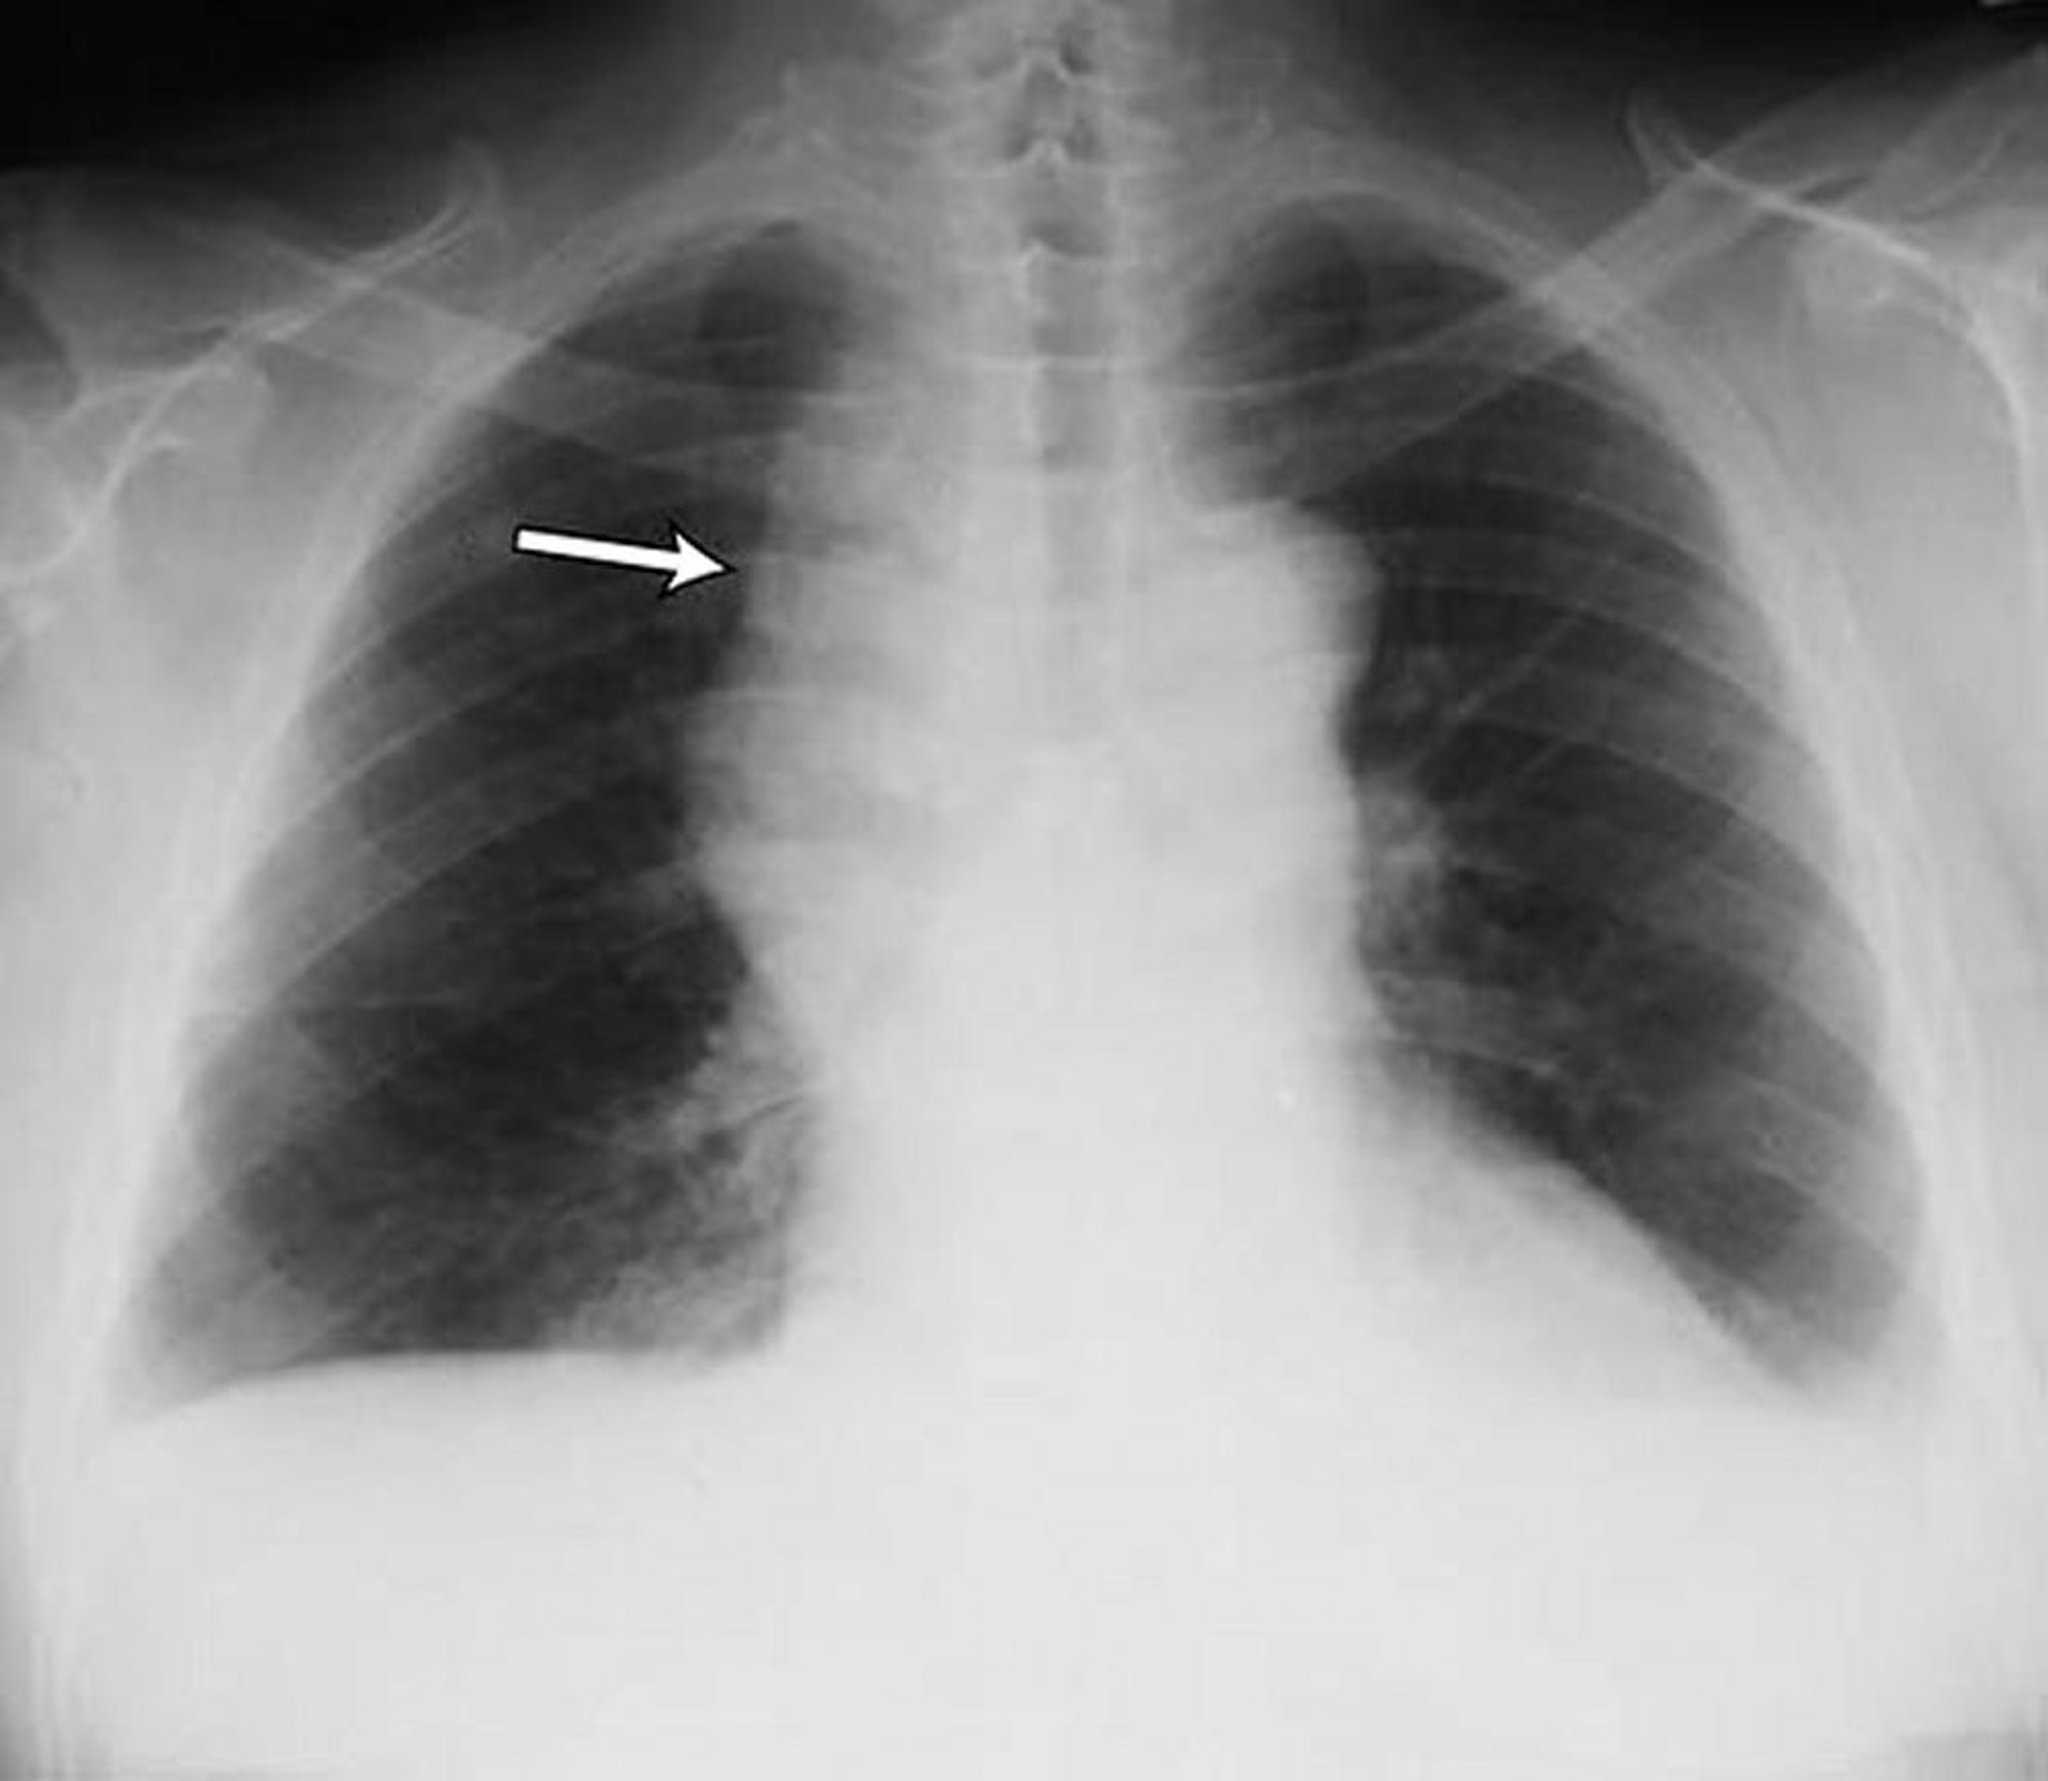

Derrame pleural leve

Derrames pleurales bilaterales leves en un paciente con linfoma no Hodgkin. Ambos ángulos costofrénicos están romos. La flecha señala el mediastino dilatado a causa del linfoma.

By permission of the publisher. From Huggins J, Sahn S. In Bone's Atlas of Pulmonary and Critical Care Medicine. Edited by J Crapo. Philadelphia, Current Medicine, 2005.